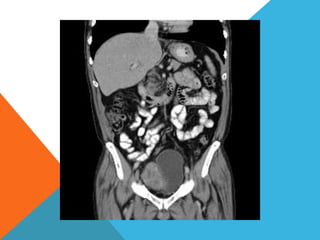

El paciente presentó síntomas de sangrado digestivo y pérdida de peso. Exámenes revelaron gastritis crónica asociada a H. pylori. Un tumor fue descubierto en una colonoscopia normal. La cirugía removió un tumor fibroide solitario, una rara neoplasia mesenquimal que usualmente crece lento y tiene bajo potencial de malignidad. El pronóstico después de la remoción quirúrgica es generalmente bueno.